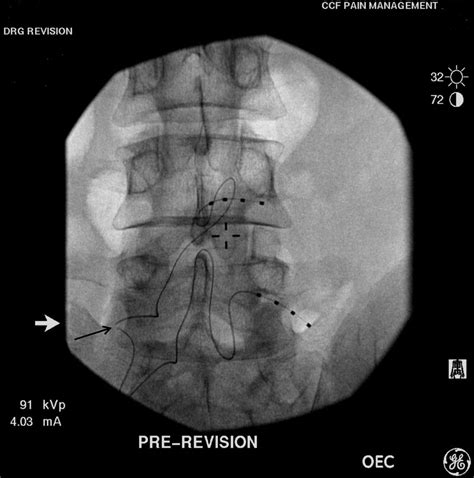

While Dorsal Ganglion Stimulation offers numerous benefits, it is not without its challenges. Some patients may experience complications during or after the implantation procedure, such as infection or device malfunction. Additionally, the cost of the procedure and the device can be a barrier for some patients. It is essential for healthcare providers to carefully evaluate each patient's suitability for DGS and discuss the potential risks and benefits.

Another consideration is the need for ongoing maintenance and follow-up care. Patients must attend regular appointments to ensure the device is functioning correctly and to make any necessary adjustments. This ongoing care is crucial for maintaining the long-term effectiveness of DGS.